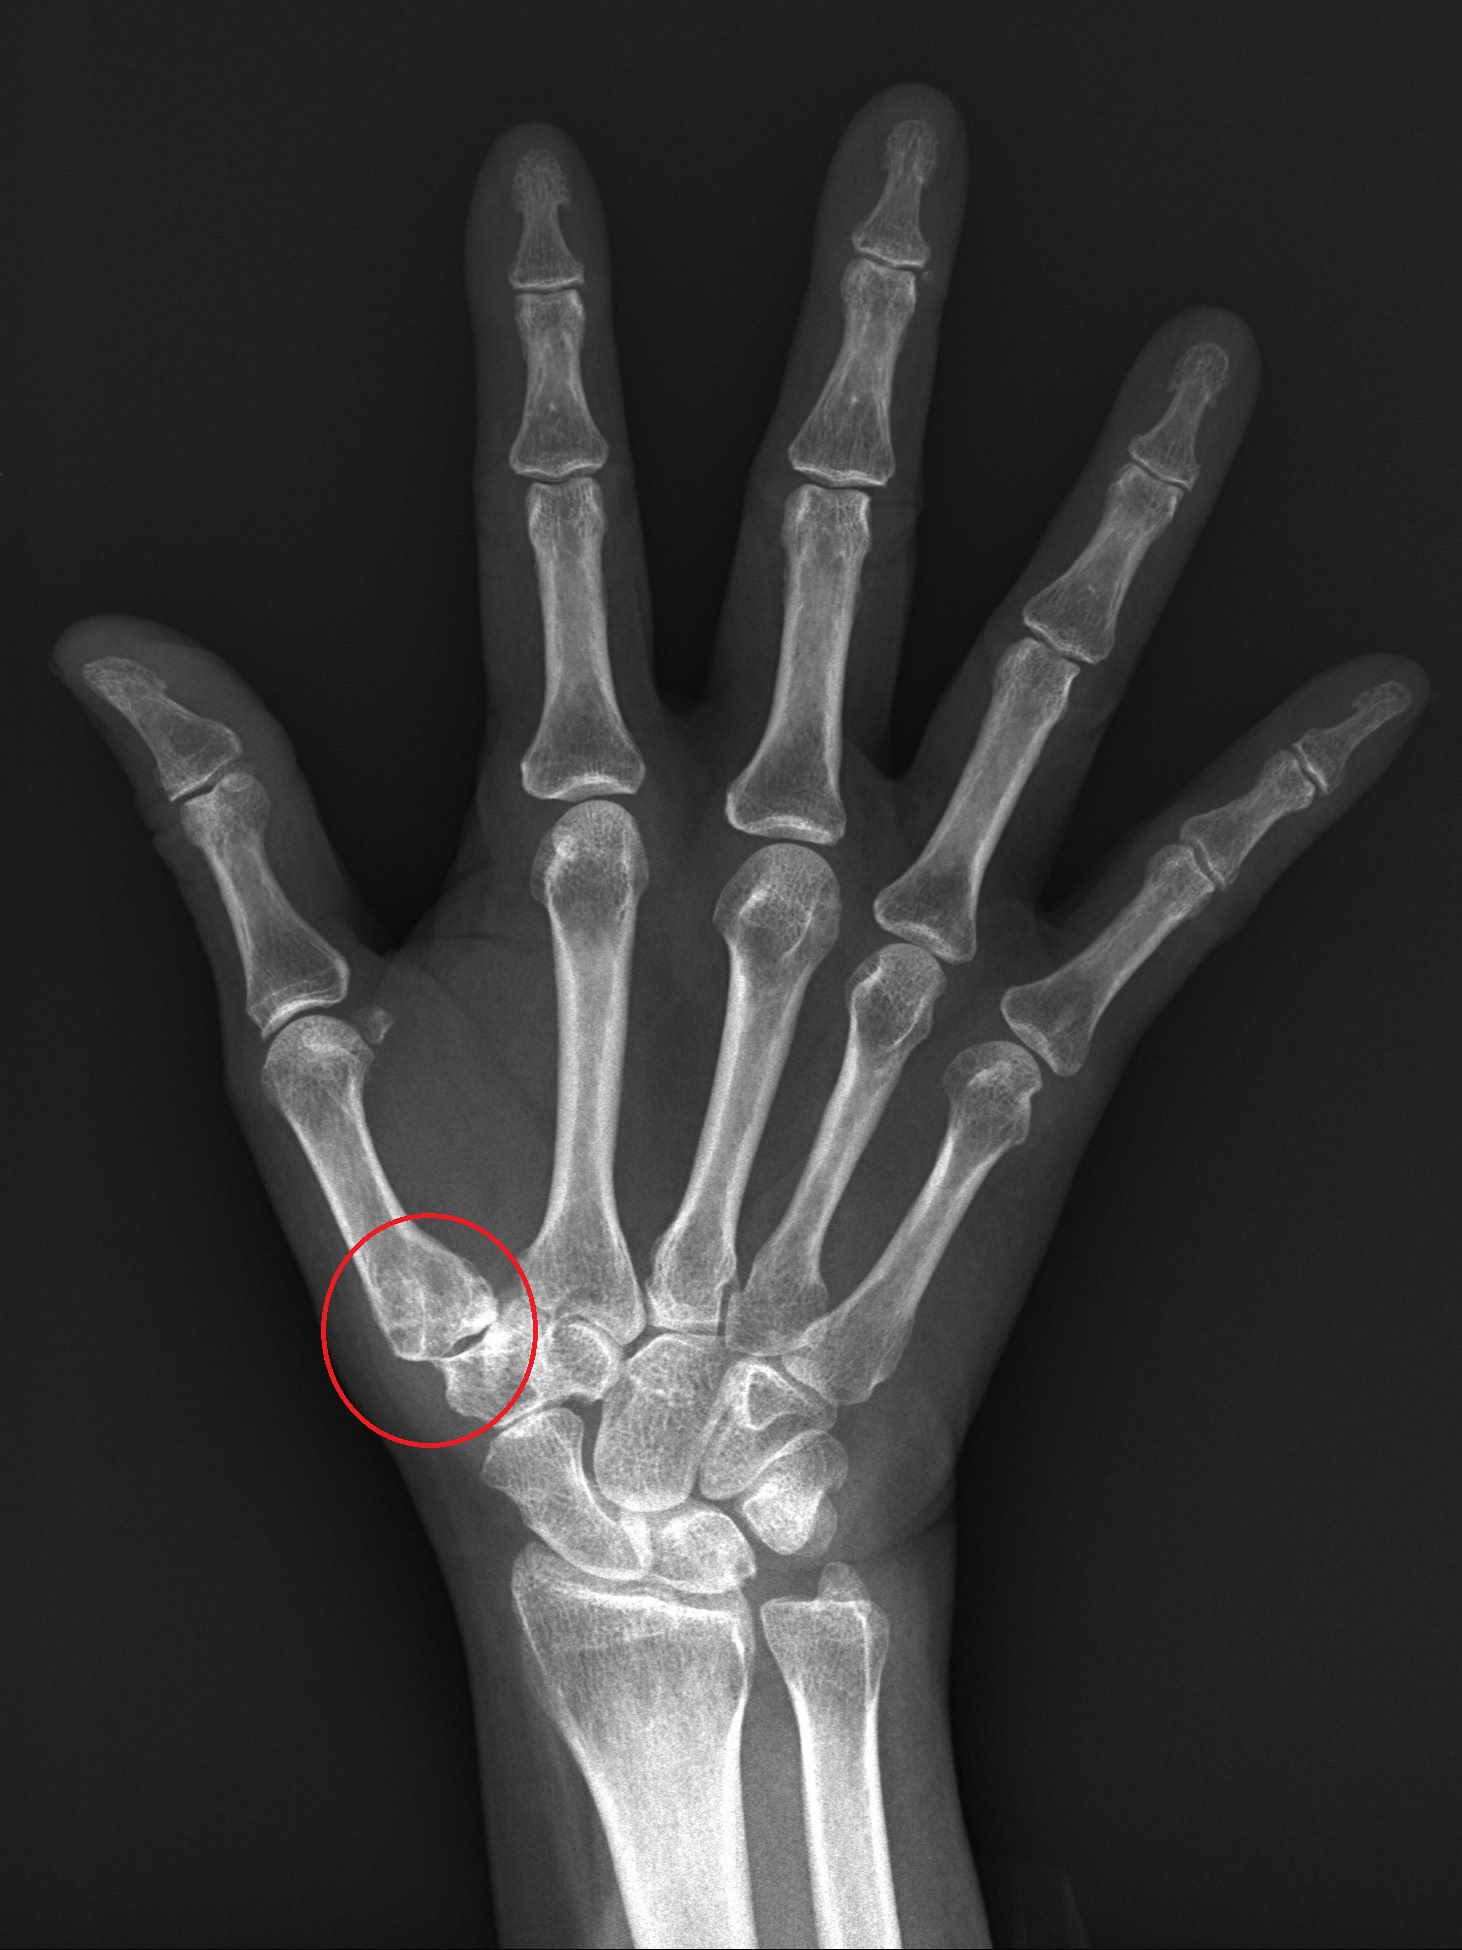

圖說 術前X光看到拇指根部關節有滑脫情形,微創手術會視情況用鈦合金或可吸收螺絲固定在第二掌骨基部

臨床會以X光判斷關節磨損程度,若程度尚輕,可以用貼紮或護腕固定,加上止痛藥物控制,但在這樣的保守治療下仍然影響生活工作機能,就可採取手術。

52歲的蔡女士從事美髮業,經常需要替人洗頭,但近來工作時經常覺得手腕疼痛,拇指無法出力,雖有去復健科就診,但止痛藥效果有限,因此到醫院骨科就診。X光發現,蔡女士的手腕因長期使用導致拇指腕掌關節磨損病變,導致她稍一施力關節就會脫離軸心。醫師以新式的微創手術將關節復位,不但不用住院,順利消除疼痛,也恢復工作機能。